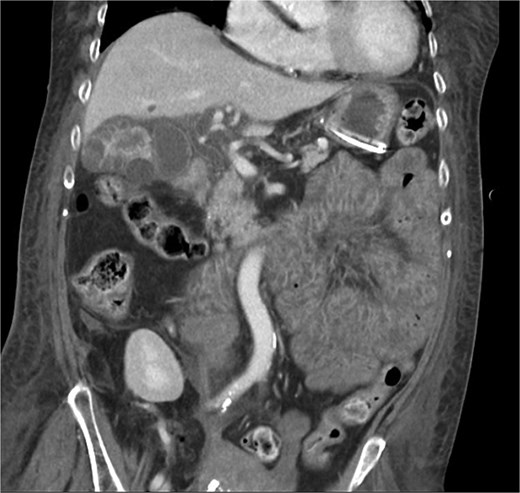

A 63-year-old female with a history of developmental delay, hypertension, hyperlipidemia, paroxysmal atrial fibrillation, hyperparathyroidism status post-parathyroidectomy, and ESRD on intermittent hemodialysis who presented for a scheduled left kidney transplant. Her post-operative course was complicated by subcapsular hematoma resulting in significant blood loss and requiring resuscitation in the trauma-surgical intensive care unit (TSICU); acute hypoxic respiratory distress on post-operative day (POD) 2, necessitating reintubation and escalating vasopressor support; and bacteremia and xanthogranulomatous cholecystitis identified on POD 3, confirmed by imaging (Figs 1 and 2) and blood cultures positive for Klebsiella pneumoniae and Enterobacter cloacae with Cefotaxime-Munich (CTX-M) resistance.

CT chest abdomen pelvis with IV contrast axial view. Gallbladder wall hyperenhancement and multiple intramural hyperattenuating nodes are again apparent in axial imaging.

XGC is typically diagnosed through imaging and histopathological examination. In this case, computed tomography (CT) revealed findings consistent with XGC, including gallbladder thickening and inflammatory changes [3]. However, definitive diagnosis was confirmed by blood cultures and the clinical course. The overlapping features with cholecystitis and biliary tract malignancies pose diagnostic challenges, particularly in acutely ill patients. In transplant recipients, where symptoms may be atypical and infection progresses rapidly, clinical suspicion and early intervention are paramount.